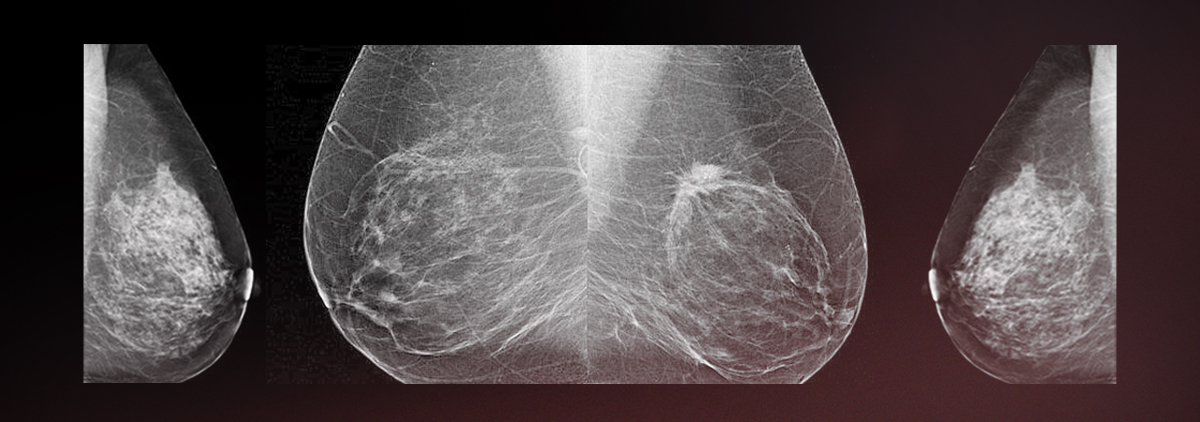

Аномалии молочной железы: медицинские примеры и визуализация

Раздел: Мудрость в деталях